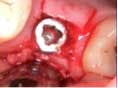

Case 1: Osteotome sinus lift with simultaneous implant placement

A 53-year-old female with a medical history of hypothyroidism, seasonal allergies, and asthma taking Synthroid and Singula presented to my office with pain in No. 3, failed root canal therapy, and a fracture. The tooth was deemed hopeless and extraction and implant placement was treatment planned. Under local anesthesia, tooth No. 3 was sectioned into three pieces and extracted. The sockets were debrided, filled with gel foam, and closed with chromic gut sutures. Healing was uneventful. The patient did not return for two years for follow-up. A CT scan was taken, which confirmed that approximately5 mm of bone remained below the floor of the sinus. After reviewing the options with the patient, a treatment plan of an internal sinus lift (osteotome), bone graft, platelet-rich fibrin (PRF) and simultaneous implant placement was agreed upon. Under local anesthesia, a full thickness flap with two vertical releasing incisions was performed at tooth No. 3 site. A trephine bur was used to a depth of 4 mm. An osteotome was then employed to infracture the bone core, which remained attached to the Schneiderman membrane. A bone graft consisting of DFDBA, anorganic bovine bone, and PRF was used in the osteotomy to increase the vertical bone height using sequential osteotomes. After sufficient elevation, a 7x9 tapered implant was placed on low speed to 50% of the implant depth. The remaining placement of implant was done with a hand torque on 50 ncm to allow for further expansion of the alveolar housing. A healing abutment was placed using the principles of platform switching. Healing was uneventful, and integration was successful.

Case 1: Implant and osteotome bone graft through the socket with Southern Implant